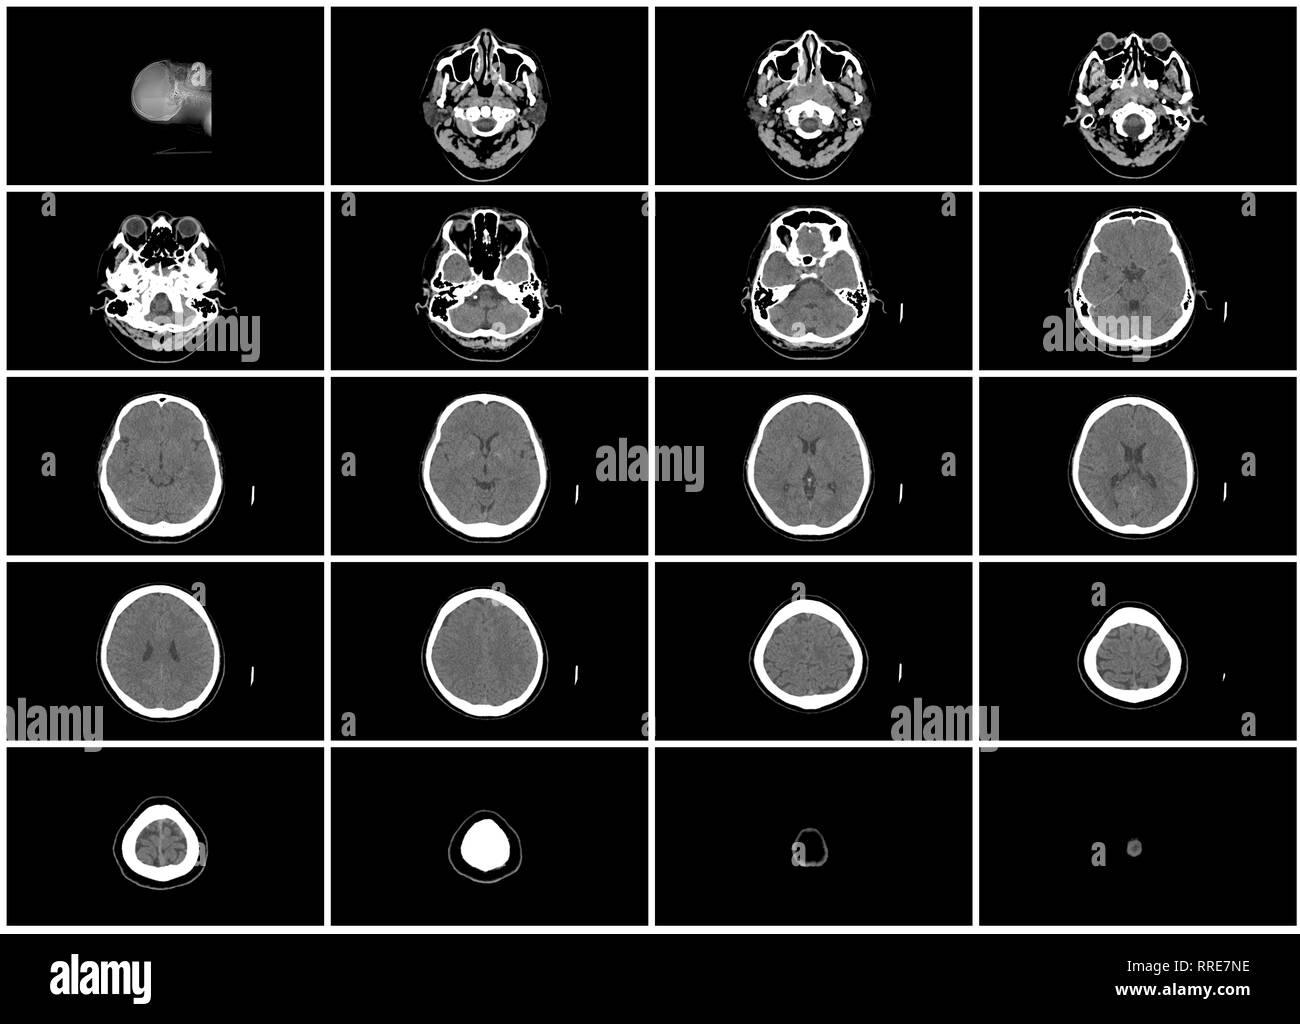

Ensemble de l'étape scanner du cerveau supérieur tête Vue de dessus axial Banque D'Imageshttps://www.alamyimages.fr/image-license-details/?v=1https://www.alamyimages.fr/ensemble-de-l-etape-scanner-du-cerveau-superieur-tete-vue-de-dessus-axial-image238185290.html

Ensemble de l'étape scanner du cerveau supérieur tête Vue de dessus axial Banque D'Imageshttps://www.alamyimages.fr/image-license-details/?v=1https://www.alamyimages.fr/ensemble-de-l-etape-scanner-du-cerveau-superieur-tete-vue-de-dessus-axial-image238185290.htmlRFRRE7NE–Ensemble de l'étape scanner du cerveau supérieur tête Vue de dessus axial